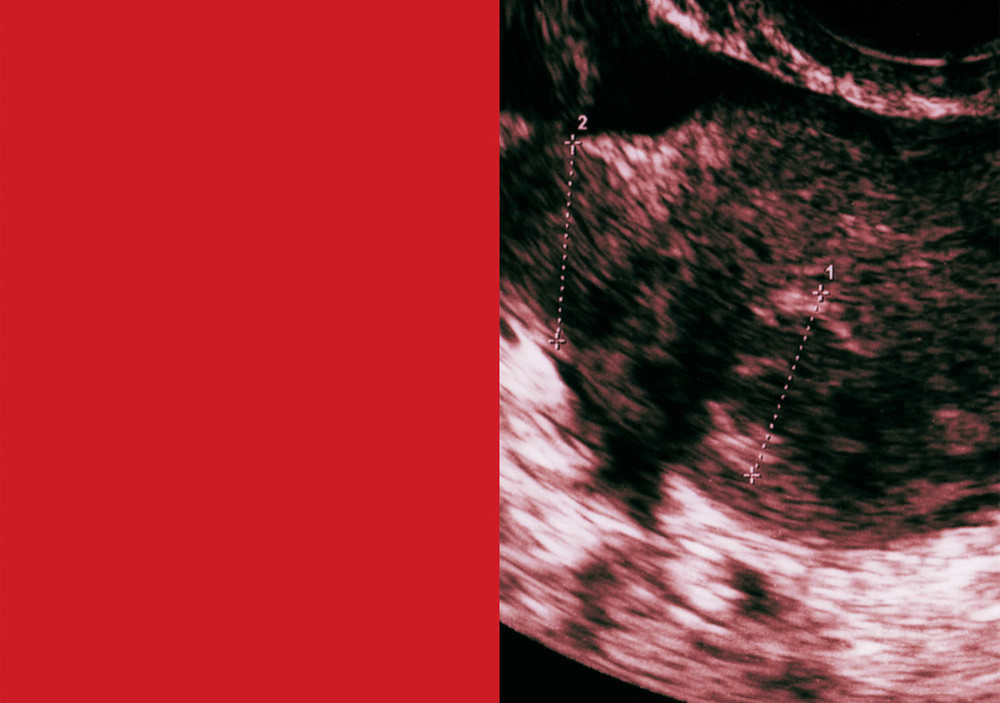

After treatment, the clinic gave Suzuki four scans depicting her fertilized eggs. Suzuki combined these with an image of a hibiscus bud, which she found on the street. “The flower had fallen before blossoming,” she remembers. “In that moment, I saw the life of a woman who could not fulfill her role.” The artist attached a thin string to the flower to resemble a tampon, and collaged it with her scans. “In the final piece, it looks like a sperm heading toward the egg.”

With both The Restoration Will and HOJO, Suzuki’s design decisions were intentional at every step—in their sequencing and editing, as well as choice of materials. In HOJO, Suzuki uses transparent paper to incorporate her medical examination data, a collection of abstract graphs. “I printed the results from when we discovered I had a blood disorder. Because of this, I was proclaimed infertile,” she says. Medical terminology can often feel cold, apathetic and detached from the human experience. In real life, the experience of infertility is layered with all sorts of emotional and societal contexts. By including this data in an evocative and ghostly sequence, Suzuki created a juxtaposition, and in turn, the project became transformative. By repurposing fragments from her diagnosis, the artist reframed it into a more relatable human experience.